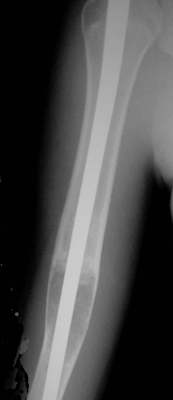

Zwei Jahre nach der Operation, die Patient ist jetzt 18 Jahre alt, hat die Cyste sich spontan verschlossen. Ein ganz kleine Restcyste ist verblieben, aber nicht mehr aktiv. Die Dicke der Corticalis hat sich wieder normalisiert, der Nagel kann entfernt werden.